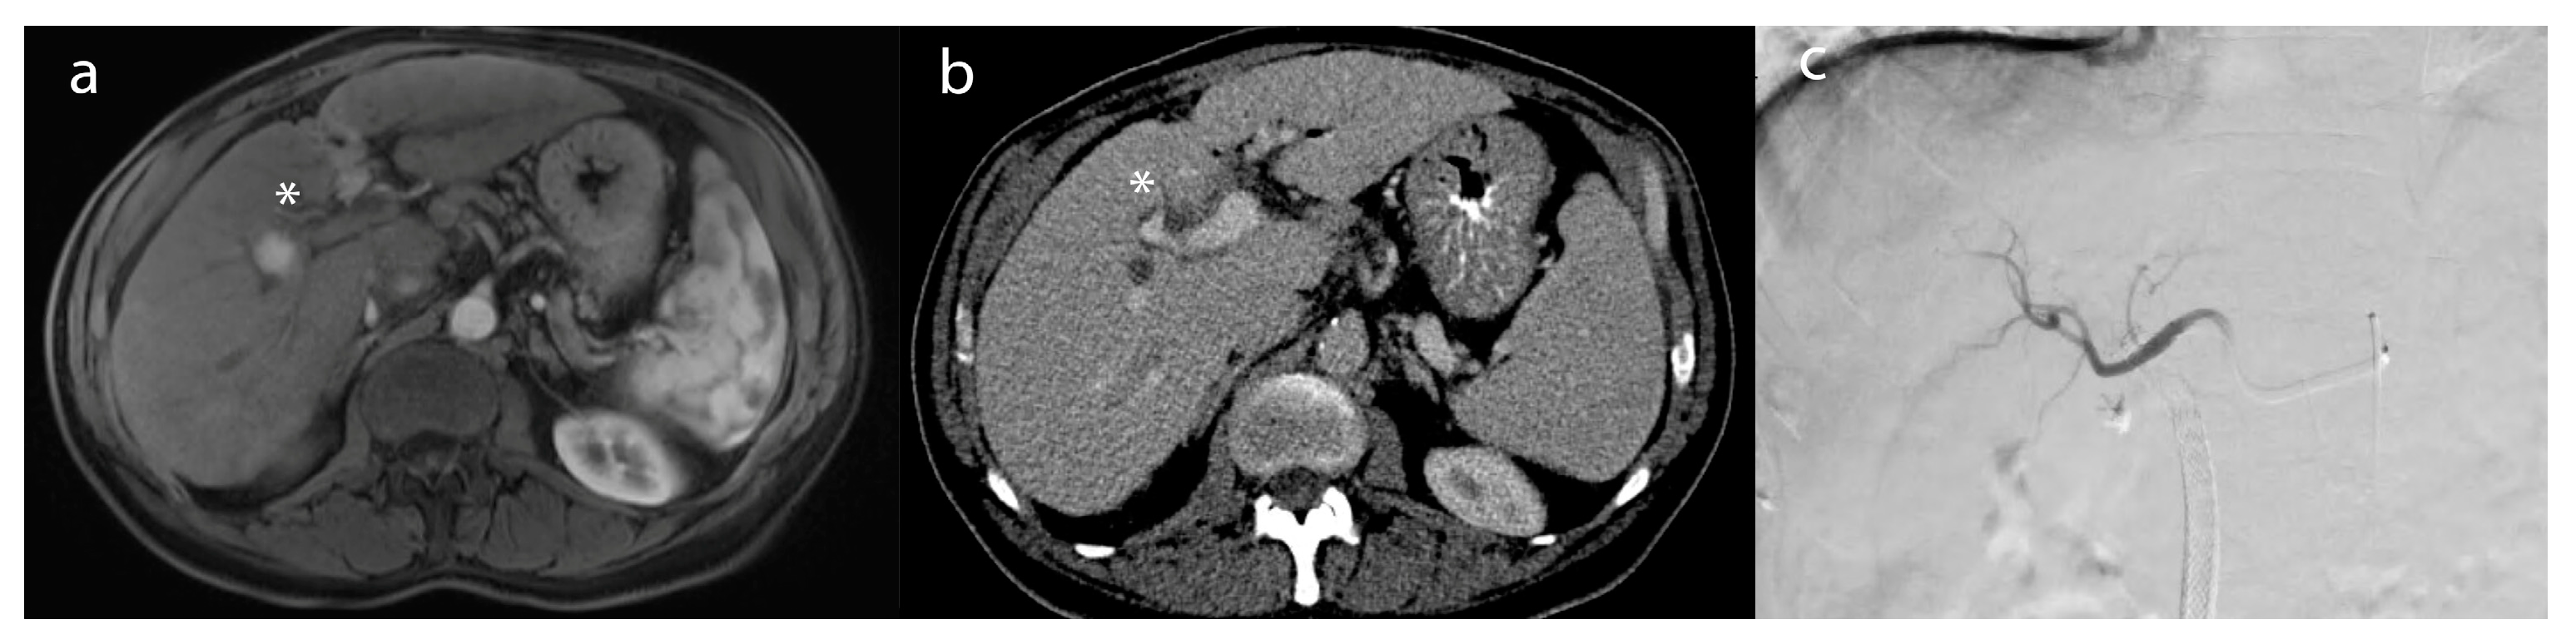

Figure 2. A 55-year-old male patient with (a) a lesion in segment 6 biopsy–proven as hepatocellular carcinoma (*)—on post-contrast T1-weighted imaging. (b) After microwave ablation, the lesion (*) demonstrated a lack of enhancement compatible with a complete radiographic response on the 1-month follow-up MRI (c) intraprocedural treatment CT of microwave ablation.

Ablative therapies include different procedures, such as percutaneous ethanol injection (PEI), radiofrequency ablation (RFA), microwave ablation (MWA), and cryoablation [3,4]. However, the goal of thermal ablation is to use heat extremes to induce tumor death through coagulative necrosis, eliminating undetected cancer microenvironments [37]. The procedure can be performed under moderate sedation or general anesthesia, and it involves the use of a percutaneous probe that navigates to the region of the tumor under CT or MRI guidance. In the context of RFA, the probe delivers frictional high-frequency alternating current to the target tissue, generating heat and, ultimately, the coagulative necrosis of the tumor. Temperatures (50–100 °C) produced by RFA denature proteins, disrupt cellular membranes, and induce thermal coagulation, leading to tumor cell death(Figure 2) [37,38]. After the procedure, patients are usually monitored through multiphasic CT or magnetic resonance imaging (MRI) to evaluate imaging response (Figure 2b). This assessment is typically done 1 month after the procedure. RFA has gained recognition as a well-established therapeutic approach due to its effectiveness, reproducibility, minimal incidence of complications, and widespread accessibility [39]. MVA, which employs electromagnetic energy to induce tumor cell injury, can also be particularly advantageous for liver tumors, due to its enhanced and predictable convection profile, sustained higher intratumoral temperatures, quicker ablation durations, and feasibility of treating multiple lesions, concurrently, using multiple probes [39,40,41].